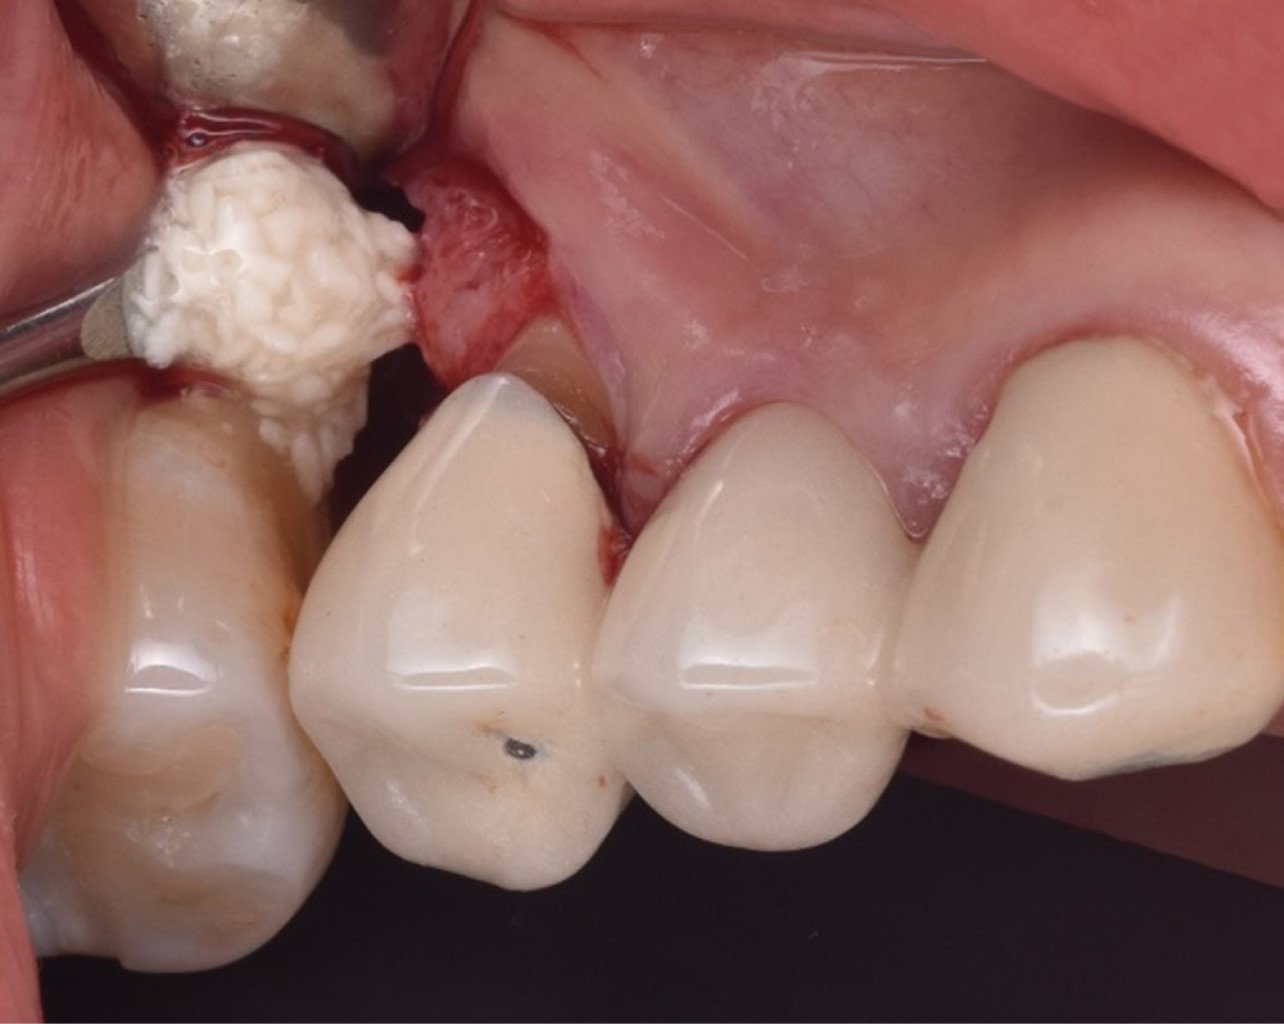

Las proteínas derivadas del esmalte (Emdogain®) se obtienen por medio de la odontogénesis en el periodo de yema de la dentadura porcina; la proteína principal es la amelogenina que presenta una biocompatibilidad con las proteínas del esmalte humano. Los cultivos in vitro han demostrado que Emdogain® al ser agregado a los fibroblastos causa una mejora en la producción de proteínas y colágeno, mineralización y proporciona condiciones favorables a la matriz, proliferación celular, migración, diferenciación y síntesis (Figuras 1, 2, 3, 4, 5 y 6). La capacidad osteogénica se relaciona de manera directa con las proteínas que contiene y esto produce una capacidad osteoinductiva y puede contener factor de crecimiento transformante beta y proteína morfogénica ósea (BMP, por sus siglas en inglés) aunque en menor cantidad.10

Figura 1

Figura 2

Figura 3

Figura 4

Figura 5

Figura 6